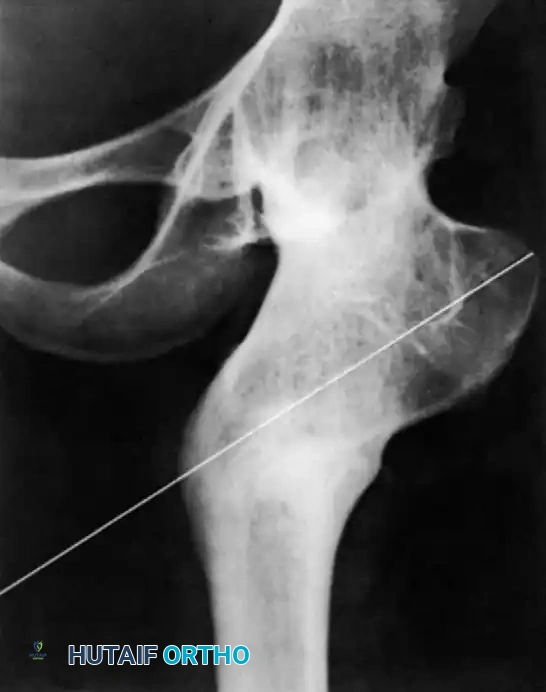

تمثيل شعاعي وتخطيطي لعمليات قطع عظم الفخذ الداني لدعم الحوض

ومن العمليات البالغة الأهمية أيضاً عملية قطع عظم الفخذ الداني الداعمة للحوض، والتي تقوم بتوجيه محور عظمة الفخذ لتستند مباشرة على الحوض، مما يوفر نقطة ارتكاز قوية ومستقرة تسمح للمريض بالمشي وتحمل الوزن رغم غياب رأس عظمة الفخذ الطبيعي.

صورة شعاعية بعد الجراحة تظهر قطع عظم الفخذ الداني بزاوية عالية